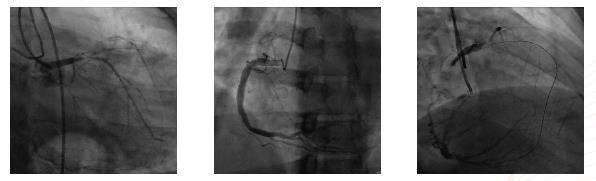

“我们给患者做了冠脉造影显示,他的前降支、对角支、回旋支均为病变血管,前降支开口100%齐头闭塞,远端经右冠脉逆行显影,这在医学上称为慢性闭塞性病变,”心内科三病区副主任孙淑艳介绍,这种病变在冠状动脉介入手术中属于最高难度手术,手术的成功率取决于患者血管的病变情况。

由于该患者闭塞病变无明显残端,闭塞长度较长,无法获得真实的血管的走行情况,且病变内部结构复杂,心内科团队通过“正、逆向”介入技术仍未能开通血管、置入支架,于是转而选择进行杂交冠状动脉血运重建治疗(HCR)。

该手术采用“分期式”HCR完成,北京大学人民医院心外科专家陈彧教授首先成功为患者实施小切口搭桥手术,采用左胸前外侧第 4、5 肋间小切口,胸腔镜辅助下完成手术。切口愈合后,包医一附院心内科专家裴汉军团队择期为患者实施了冠状动脉介入治疗,术前冠脉及桥血管造影提示患者内乳动脉桥血流通畅,前降支远端显影良好,吻合口质量极佳,之后成功置入一枚支架。术后患者恢复良好,顺利出院。